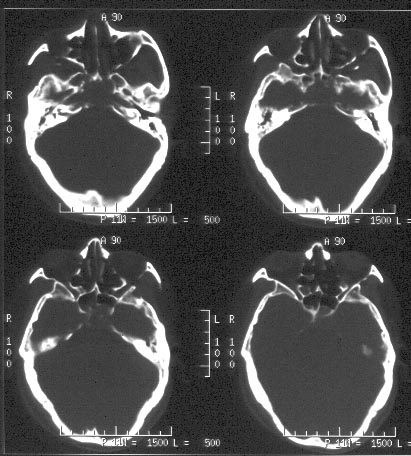

男性,48岁。吸涕带血2月余。

ct平扫:鼻咽腔明显狭窄,鼻咽顶壁、顶后壁、后壁、双侧壁增厚,右侧甚,右侧鼻咽旁间隙、颈动脉间隙见软组织肿物占据,肿物向前达后鼻孔,向下达右侧口咽,肿物向中颅窝侵犯致广泛颅底骨质破坏:包括枕骨斜坡、枕大孔、蝶窦、鞍底、双侧蝶骨大翼、双侧岩尖、双侧翼板。蝶窦、蝶鞍为软组织肿物占据,左侧海绵窦稍增厚。左侧鼻咽旁间隙、颈动脉间隙未见明显异常。

ct诊断:考虑鼻咽癌,并口咽受侵犯、颅底骨质破坏。